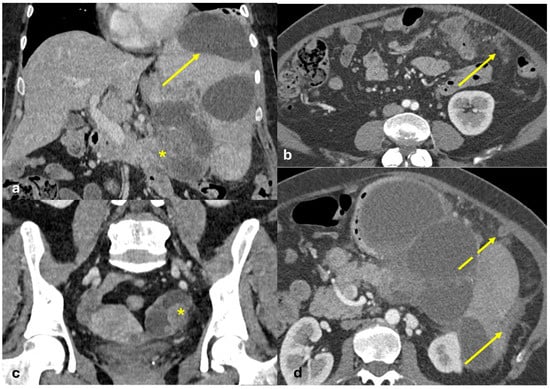

- Plaque pattern: confluent nodular plaques, typically involving the lower surface of the right diaphragm (Figure 3);